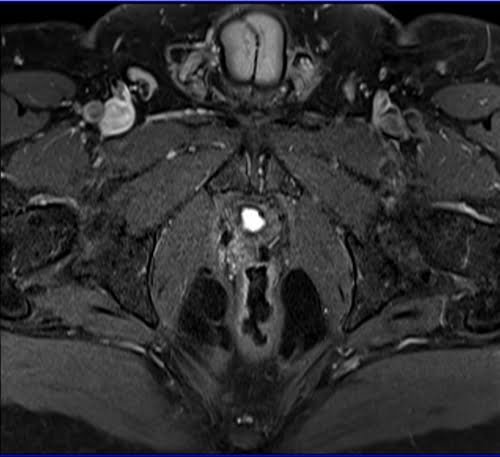

Prostatectomy patients prostate MRI T1 fat sat post contrast axial high resolution images